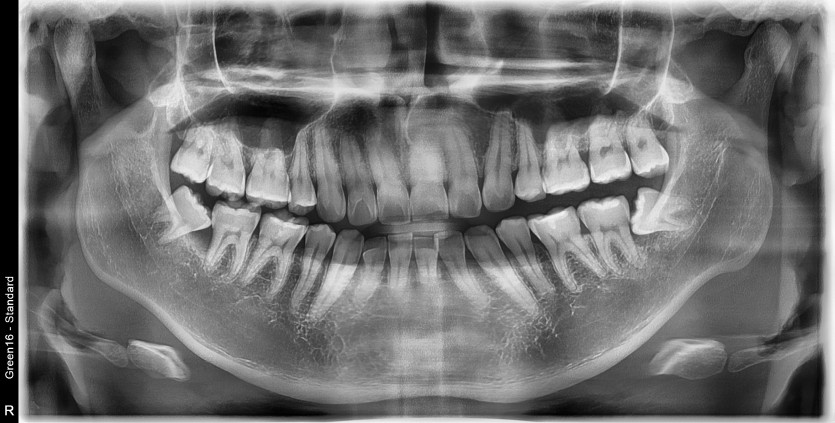

#28,38 사랑니 발치

구강 외과 전문의가 당일 발치했습니다.